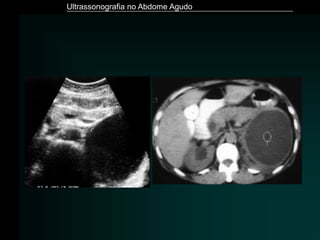

Pancreatite Aguda

• Exame de imagem de eleição - Tomografia Computadorizada

• ULTRASSONOGRAFIA

– Limitação - distensão gasosa

– Detecção de litíase biliar

– Aumento volumétrico

– Hipoecogenicidade difusa ou focal

– Dilatação do Wirsung

– Perda de definição dos limites

– Áreas hiperecogênicas – hemorragia

– Coleções – às vezes o único achado

Ultrassonografia no Abdome Agudo

Hayes. Eur Radiol (2004) 14:L123–L137